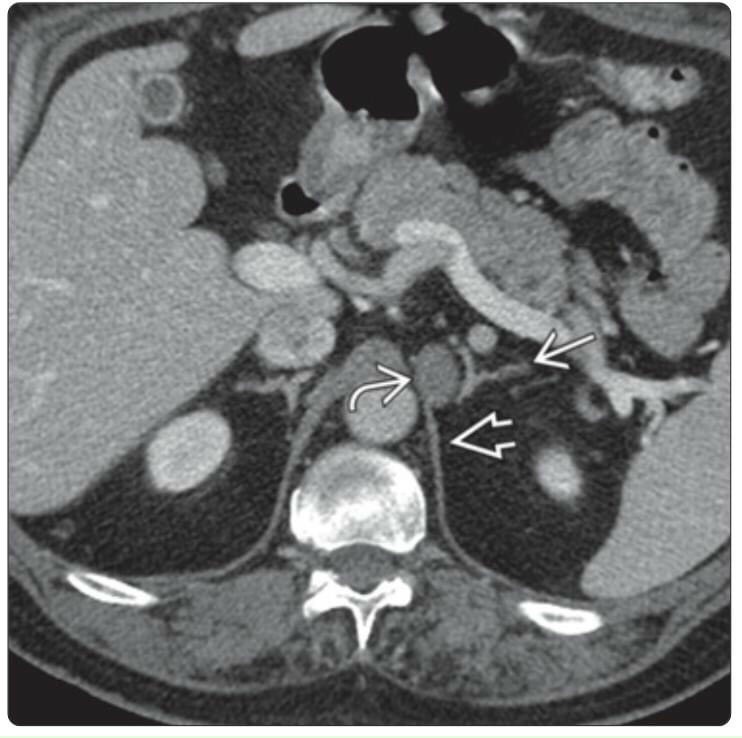

Hình ảnh nang tuyến thượng thận

Hình ảnh nang tuyến thượng thận

Hình ảnh nang tuyến thượng thận

Hình ảnh nang tuyến thượng thận